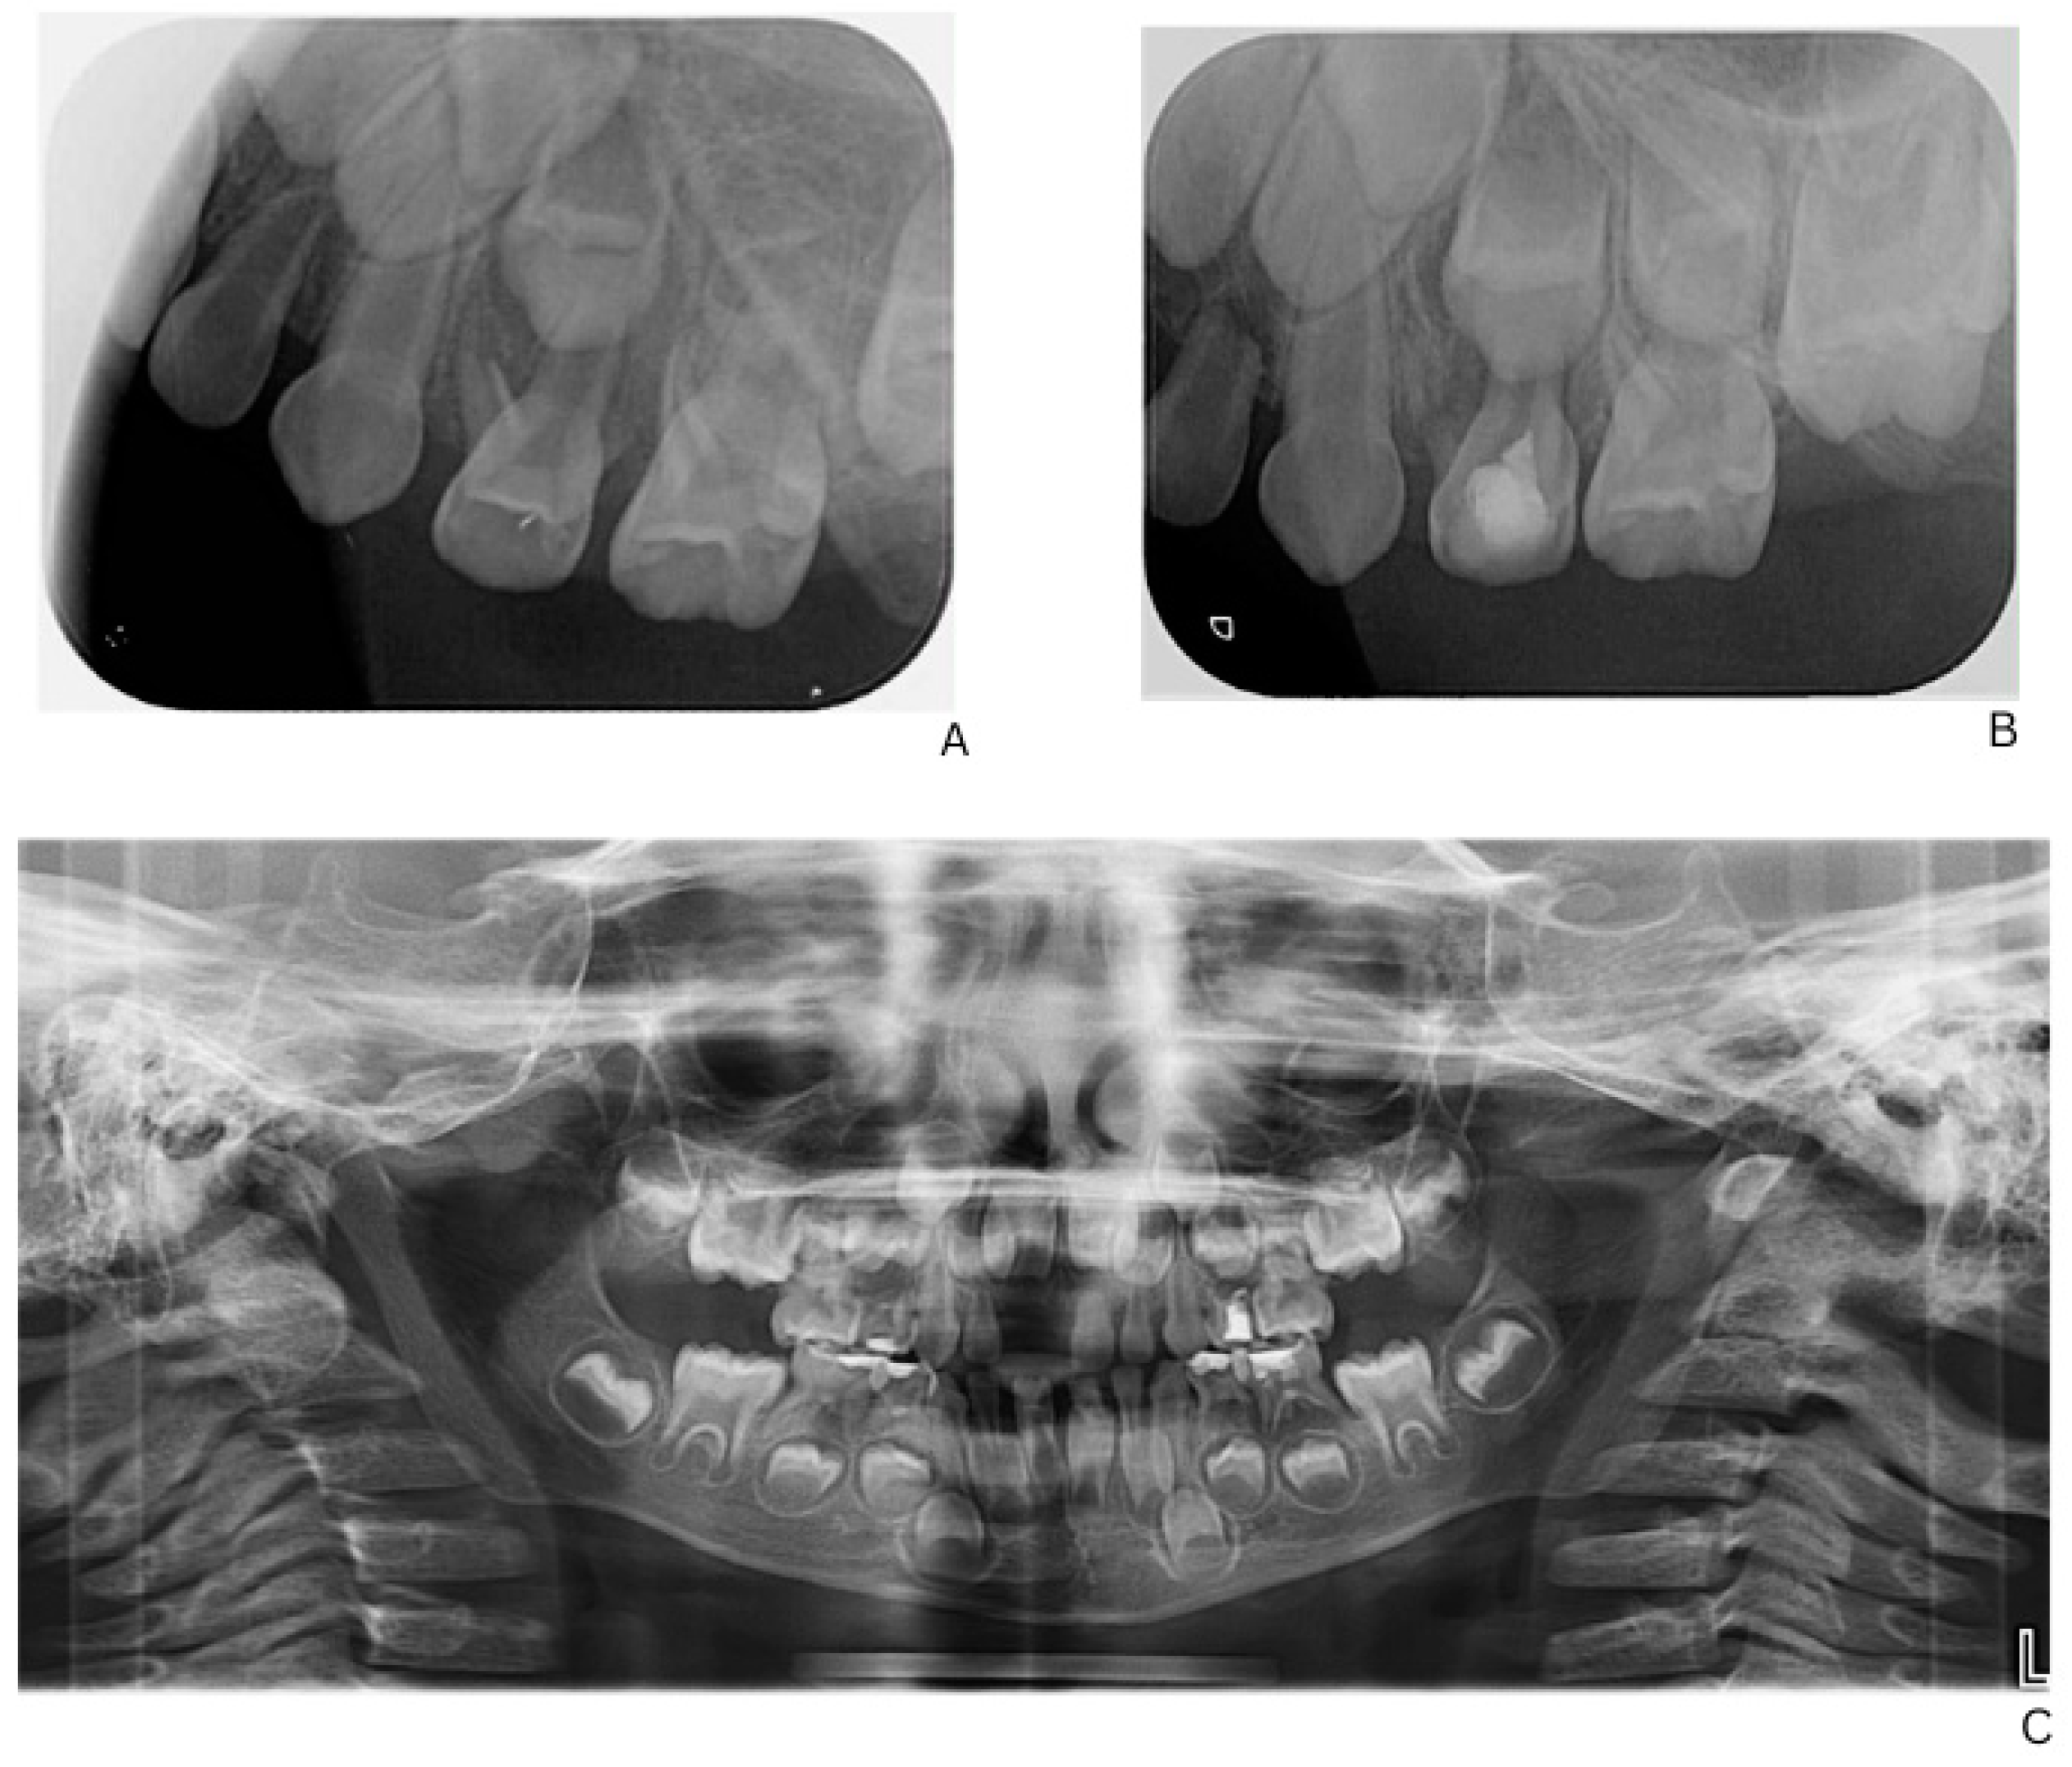

Figure 2.

Radiographic follow-up of upper left first primary molar showing initial and post-treatment periapical status, and panoramic overview. (A) Pre-treatment periapical radiograph of the upper left first primary molar. (B) Post-treatment periapical radiograph showing healing after formalin–resorcinol endodontic protocol and glass–ionomer cement restoration. (C) Panoramic radiograph (OPG, 2025) demonstrating overall progression of dental treatment and status of other primary molars.

Initial dental management focused on infection control and the preservation of dental function. A formalin–resorcinol endodontic protocol was applied to the affected primary molars, followed by long-term glass–ionomer cement restorations (VOCO GmbH, Cuxhaven, Germany) (Figure 2). Due to the child’s uncooperative behavior, treatment required multiple short appointments with behavioral guidance. The clinical team considered that the behavior could be gradually managed, and in agreement with the parents’ informed preference, treatment was carried out in short, sequential sessions rather than under general anesthesia or sedation.

Given the patient’s limited cooperation, the lack of alternative methods capable of effectively controlling the periapical inflammation in this specific pathogenic context, and the need to maintain the primary teeth until their physiological exfoliation, a resorcinol–formalin technique was selected. This approach represented the only practically effective option in a situation characterized by spontaneously developing pulp necroses in clinically intact teeth.